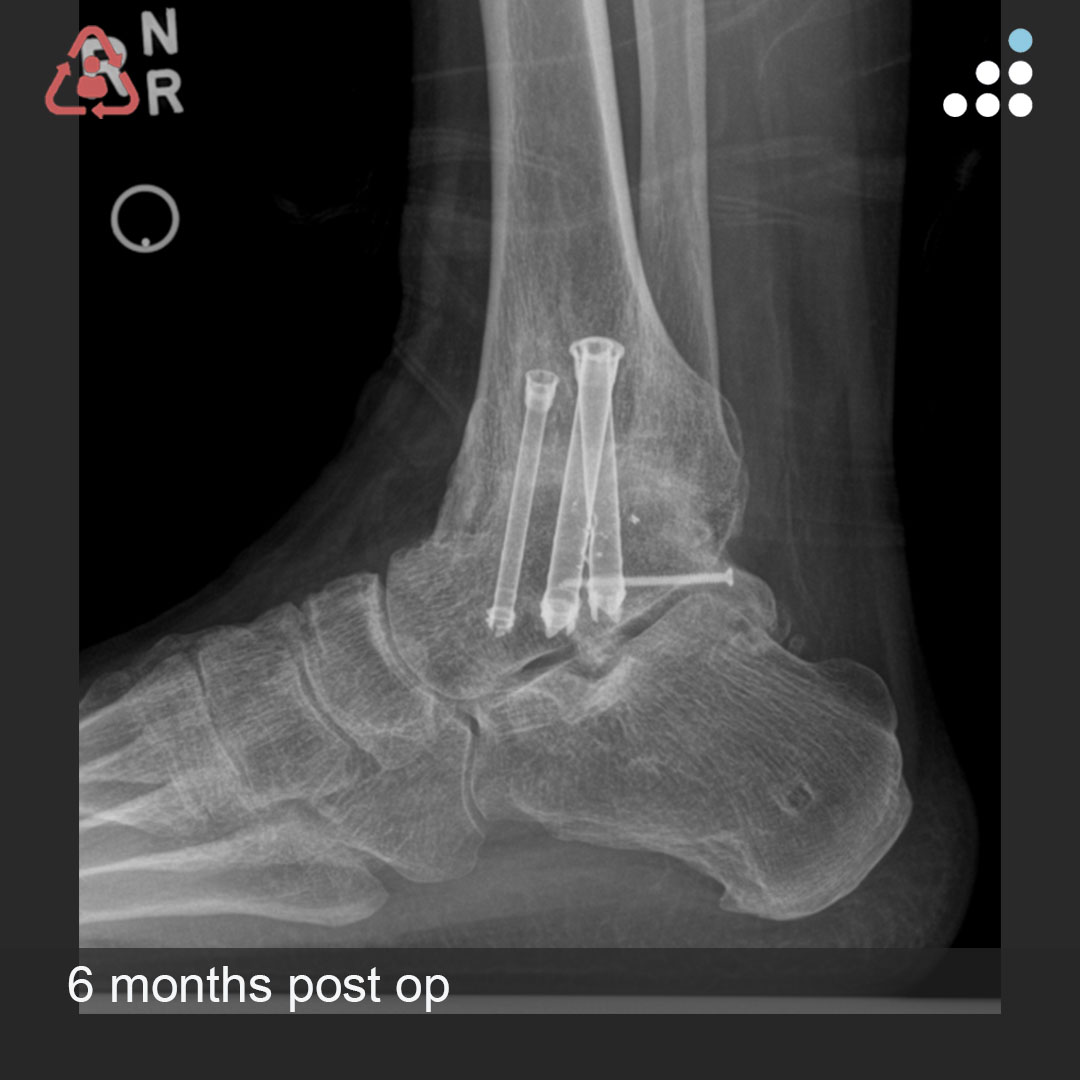

Here are intra-op & post-op images of yesterday's case by Dr. Jan Szatkowski(@orthotraumamd) & @IU_Health.

ANKLE PAIN 9 MONTHS S/P OPEN ANKLE FRACTURE-DISLOCATION IN 33M

Do you agree with the treatment? Why or why not?

Comment & keep the great conversation going!

#orthotwitter